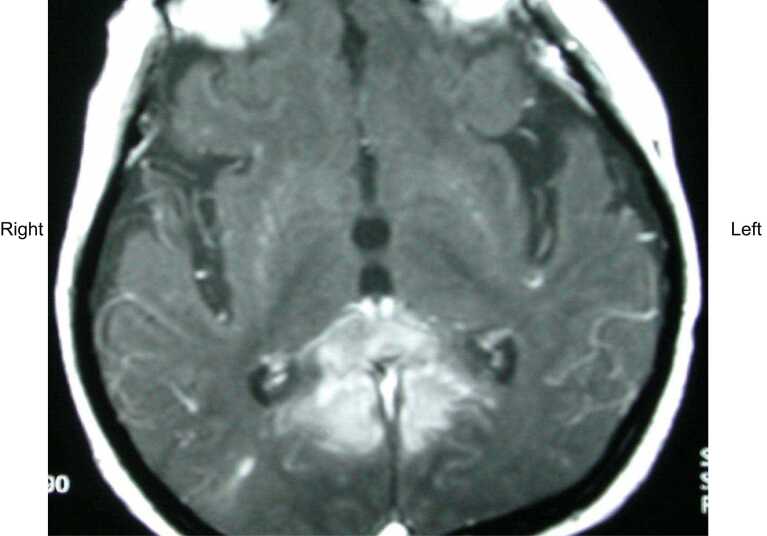

The authors report a case of varicella zoster encephalitis, mimicking a glioblastoma on Magnetic Resonance Imaging (MRI) and Magnetic Resonance Spectroscopy (MRS). The limitations of MRI/MRS, may lead to delayed treatment with antiviral agents, which can result in increased morbidity and mortality. The possibility of viral encephalitis should remain in the differential diagnosis of all patients presenting with headaches and confusion, even when imaging results are indicative of a neoplastic process.

Abstract Image